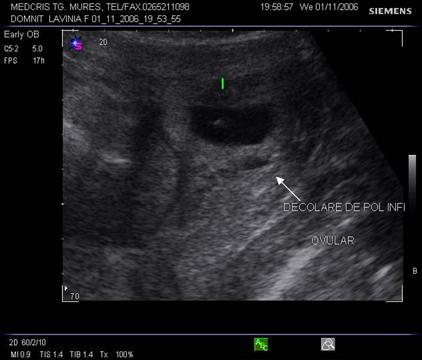

Fig nr 6 Decolare de pol inferior ( cu sageata ) la o sarcina de 7 sapt

Fig. nr. 66. Aceeasi sarcina, ca in figura precedenta, la 12 saptamani , fara imagini patologice la polul inferior ovular, marcat cu sageata